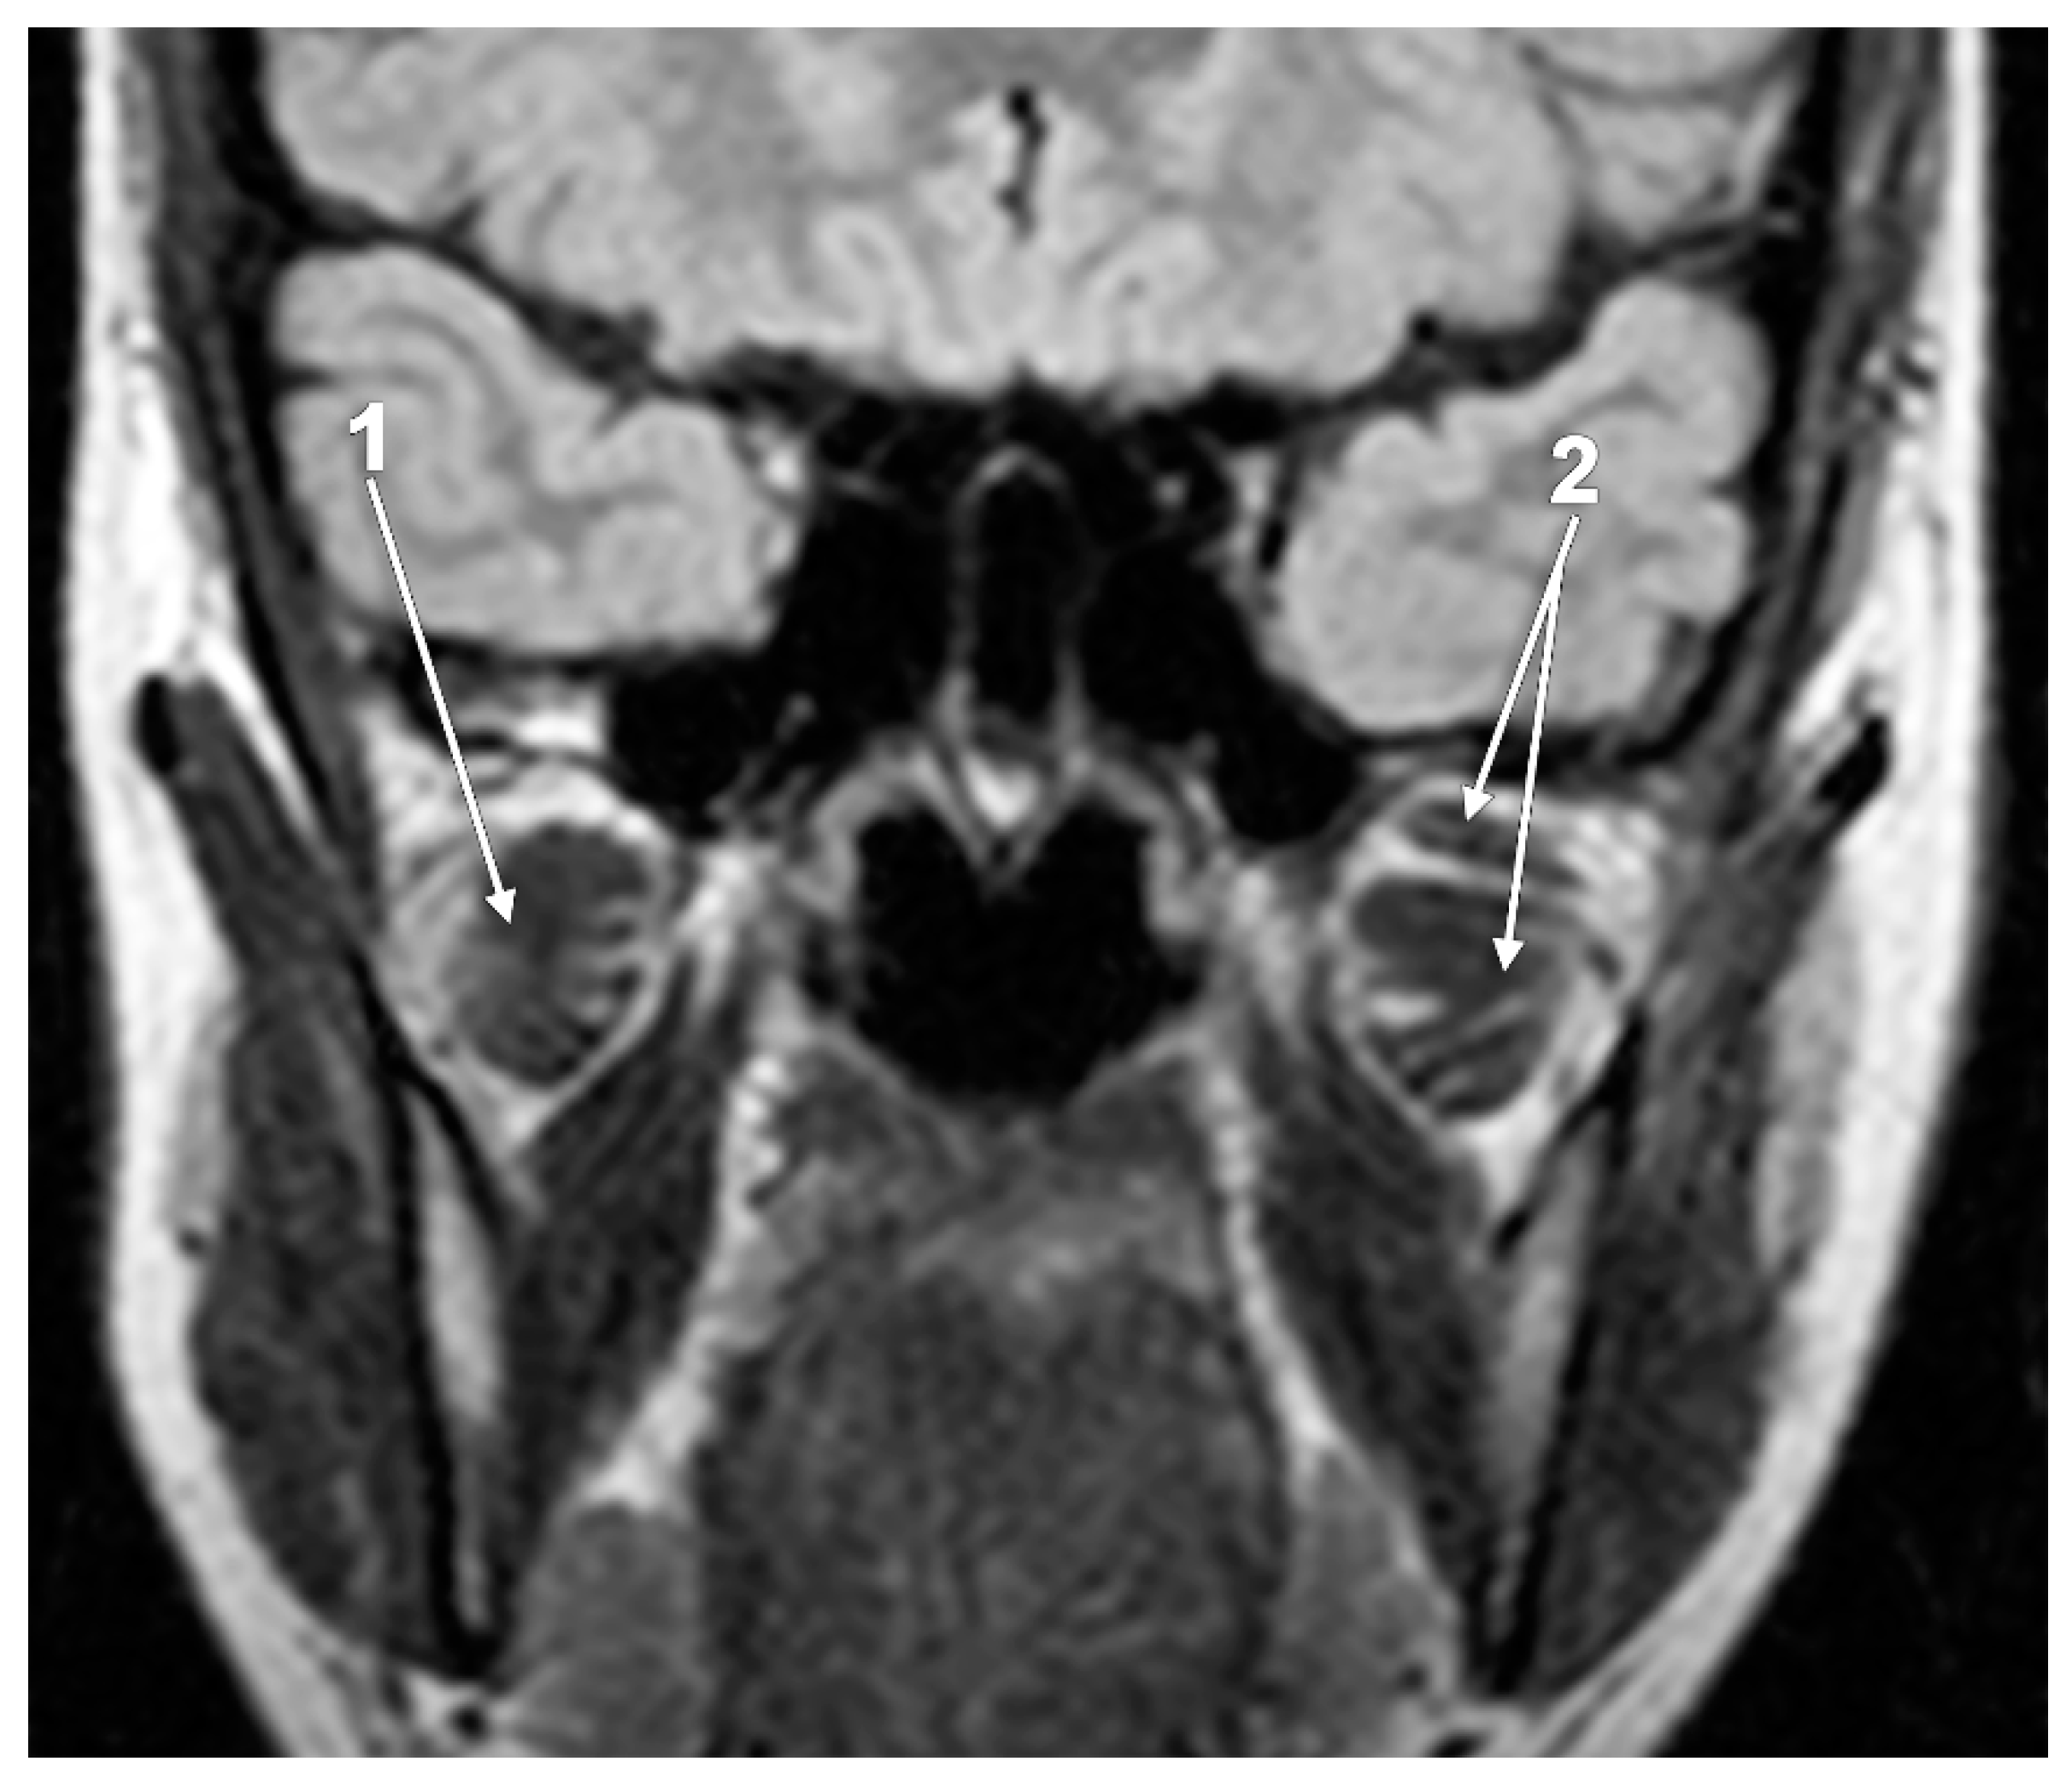

- Melke, G.S.F.; Costa, A.L.F.; Lopes, S.; Fuziy, A.; Ferreira-Santos, R.I. Three-dimensional lateral pterygoid muscle volume: MRI analyses with insertion patterns correlation. Ann. Anat. 2016, 208, 9–18. [Google Scholar] [CrossRef]

- Yilmaz, D.; Kamburoglu, K.; Arslan, R. Quantitative volume and area assessment of masticatory muscles through magnetic resonance imaging in patients with temporomandibular joint disorders. Oral Surg. Oral Med. Oral Pathol. Oral Radiol. 2023, 135, 548–557. [Google Scholar] [CrossRef]

- D’Ippolito, S.; Borri Wolosker, A.; D’Ippolito, G.; Herbert de Souza, B.; Fenyo-Pereira, M. Evaluation of the lateral pterygoid muscle using magnetic resonance imaging. Dento Maxillo Facial Radiol. 2010, 39, 494–500. [Google Scholar] [CrossRef] [PubMed]